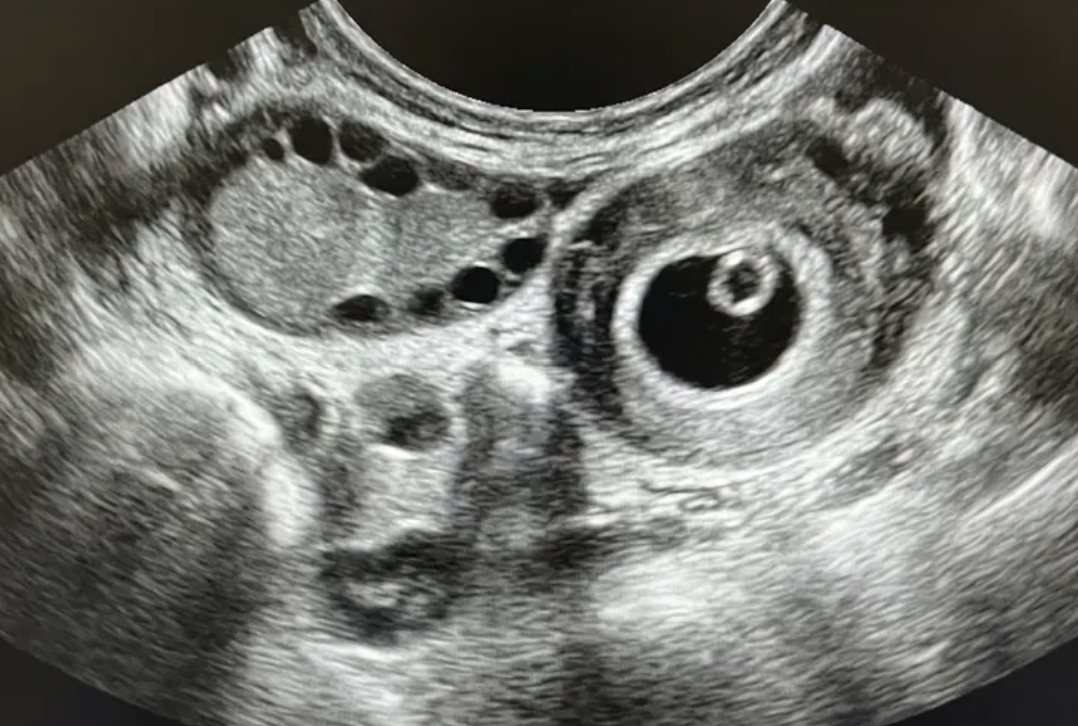

Gestação ectópica (US)

Ferramenta educacional baseada no NICE guideline NG126 (2019, atualização 2023), com abordagem conservadora. Ajuda a reconhecer sinais ultrassonográficos de gestação ectópica tubária e a lembrar a necessidade de correlação clínica e laboratorial.

Indica ectópica tubária (USTV)

Alta probabilidade (USTV)

Possível ectópica (USTV)